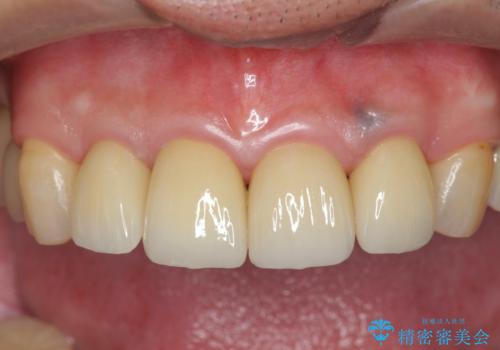

「 放置した虫歯 」 前歯セラミック治療

- 61.6万円(仮歯・ジルコニアクラウン×4・ファイバーコア ・エクストリュージョン)費用は治療当時の料金となります

虫歯の放置により、根管治療や深い虫歯に対する処置が必要になりましたが丁寧に一つづつ処置を行ったことで抜歯をすることなく歯を残すことができました。

セラミッククラウンの製作をする前に、歯内・歯周環境の整備は非常に大切です。